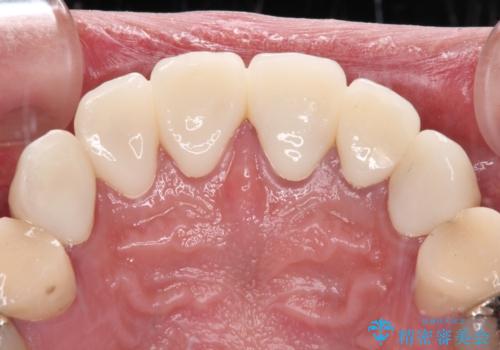

むし歯は多かったものの、歯肉の腫脹はそれほどなかったため、最小限の治療回数で治療を終えることができました。